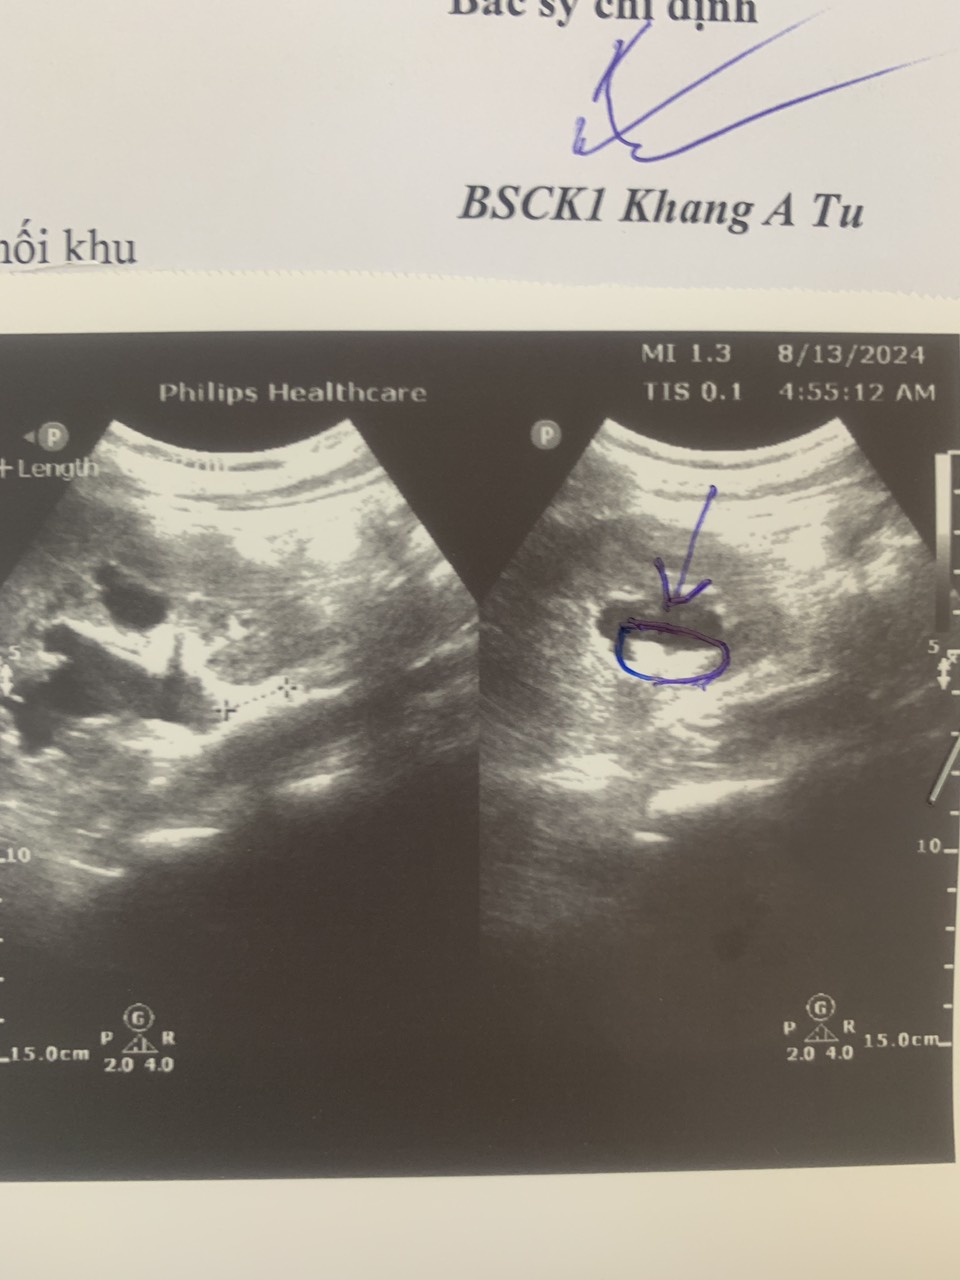

Hình ảnh siêu âm và chụp Xquang